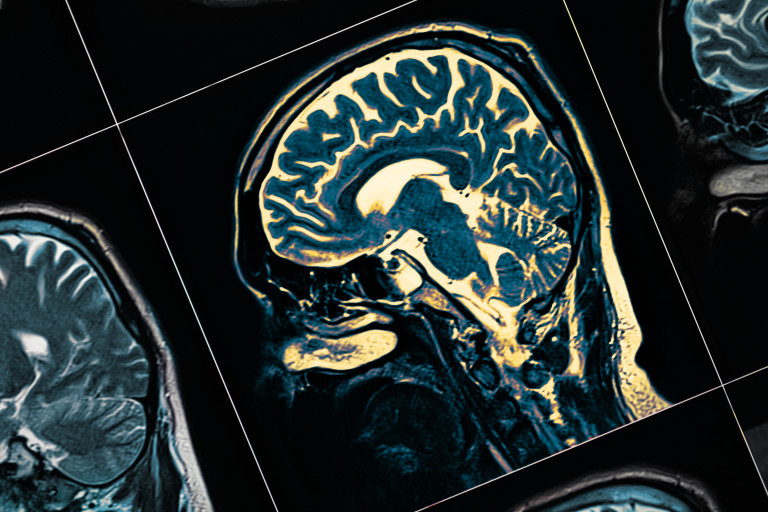

Голяма част от изследванията напоследък пък са свързани с откриването на медикамент, който да премахва образувалите се в мозъка токсични амилоидни плаки. Именно с тях се изразява болестта на Алцхаймер, а наличието им унищожава невроните и възможността да комуникират помежду си, което води до нарушаване на паметта например. Засега обаче подобно лекарство не е открито.

Когато сме концентрирани, когато създаваме или връщаме спомени в съзнанието си, в мозъка ни се наблюдават т.нар. гама вълни, които са с честота от 30 до 100 Hz. Според изследвания от преди две десетилетия, пациентите с болест на Алцхаймер имат много по-слаби гама вълни. Затова и се предполага, че това е един от ефектите на заболяването.

Наблюдава се и друг интересен ефект от светлинната стимулация на мозъка - много бързо активизиране на специален тип клетки в мозъка (микроглия), които служат за очистване от всички токсини и вредни вещества, попаднали в него, в това число и плаките. Смята се, че при пациентите с Алцхаймер, тези клетки не изпълняват своята функция, пише BBC.

Така първото откритие на учените е, че има връзка между гама вълните и клетките, които "почистват" мозъка. Тяхната стимулация чрез опогенетика при хората обаче е прекалено сложна, защото включва хирургия и генетична модификация. Затова учените търсят по-лесен и безопасен начин за постигане на същия или подобен ефект.